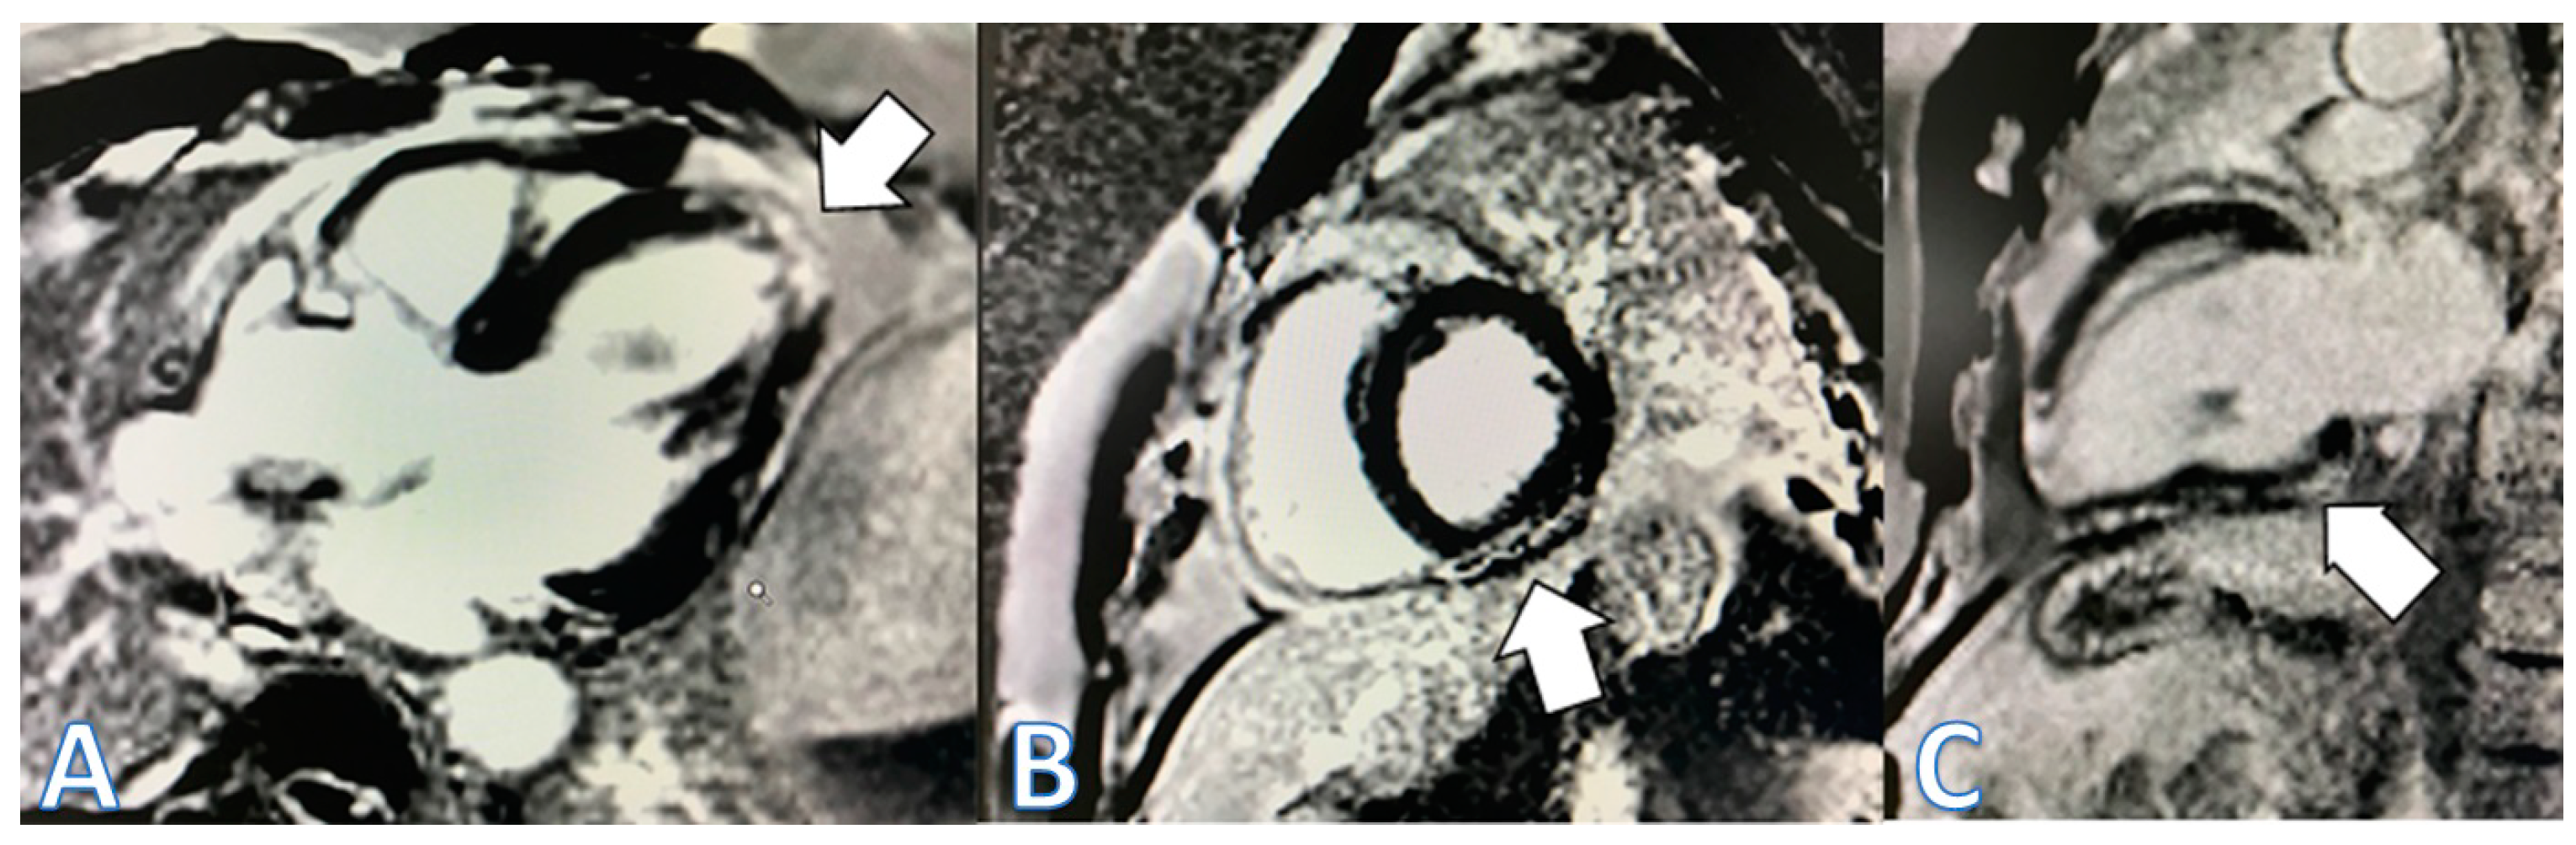

| CMR at hospitalization | LGE of both pericardial leaves and foci of late subepicardial enhancement on the basal inferolateral, lateral, and inferior walls | LGE at the level of the pericardial leaves and a basal inferolateral subepicardial focus | Edema and LGE in the lower-middle, inferolateral, and anterolateral segments | Edema and LGE at the anterolateral, basal-mid inferolateral and basal inferior segments, and intramyocardial in the mid-inferoseptal and apex segments |

| Control CMR at 3 months | Persistence of LGE on the inferolateral wall | Disappearance of LGE | - | - |

| Control CMR at 6–9 months | Persistence of LGE on the inferolateral wall | - | LGE in the inferolateral and anterolateral walls | LGE intramyocardial and subepicardial at inferolateral, anterolateral, and inferoseptal walls (reduced extent) |

| Control CMR at 2 years | - | - | LGE in the inferolateral and anterolateral walls (reduced extent) | - |